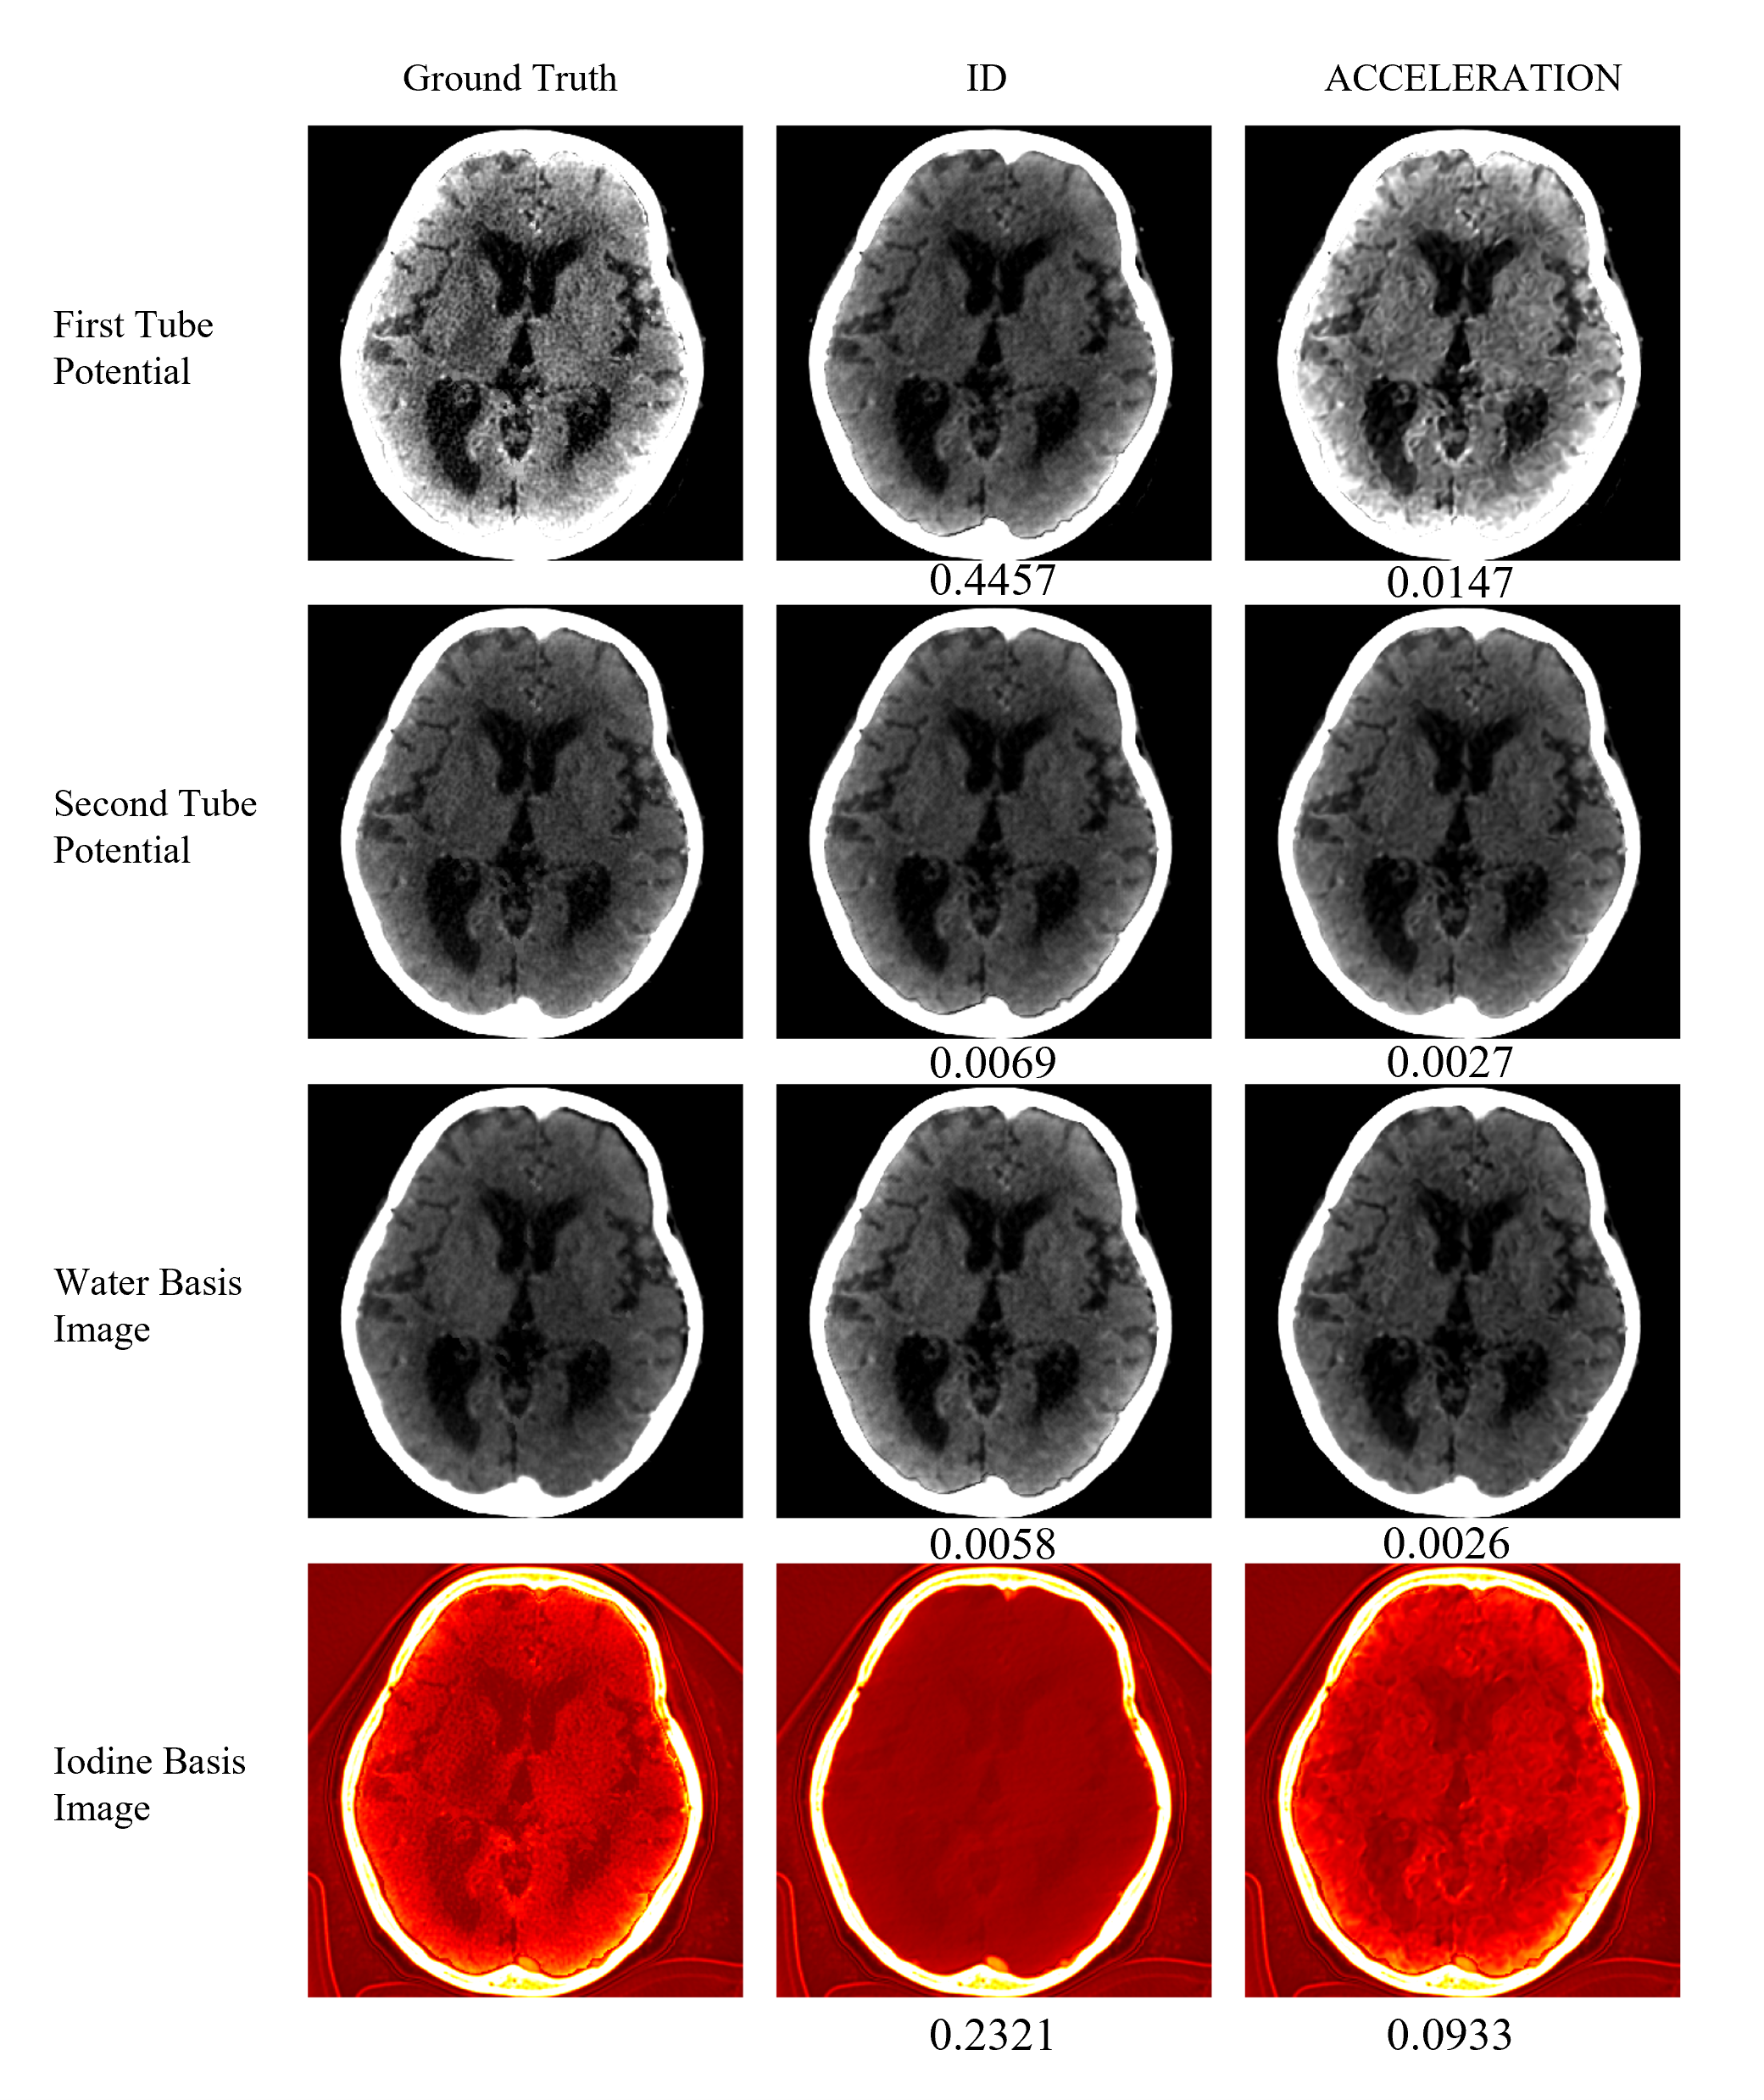

Refer to caption

Fig. 7: Material basis images. First to third column: ground truth, FBP without extrapolation and ACCELERATION. First to forth rows: CT at low tube potential with display windows [0,120] HU, CT at high tube potential with display windows [0,120] HU, water basis images with display windows [1000,1100] g/cm3𝑔𝑐superscript𝑚3g/cm^{3} and iodine basis images with display windows [0,15] g/cm3𝑔𝑐superscript𝑚3g/cm^{3}. The numbers below the image represent the NRMSE between the image and ground truth.

In this section, we perform material decomposition based on CT images at two tube potentials that are consistent in time, thereby obtaining relatively accurate material basis images. Fig. 7 shows a comparison experiment of image-domain material decomposition (ID)111To the best of the authors’ knowledge, this paper presents the high temporal resolution CT imaging based temporal extrapolation algorithm to firstly address the inconsistency in iodine concentration in sequentially-scanning DECT. Therefore, we only compares the proposed technique with direct image-domain material decomposition. In this context, the reconstruction accuracy before material decomposition has a relatively small impact on the accuracy loss caused by inconsistent iodine concentration. Specifically, Filtered Back Projection (FBP) is used as the reconstruction algorithm for comparative experiments. and material decomposition after extrapolation using ACCELERATION. It can be clearly seen that after the correction of ACCELERATION, the accuracy of material basis images after material decomposition are significantly improved.